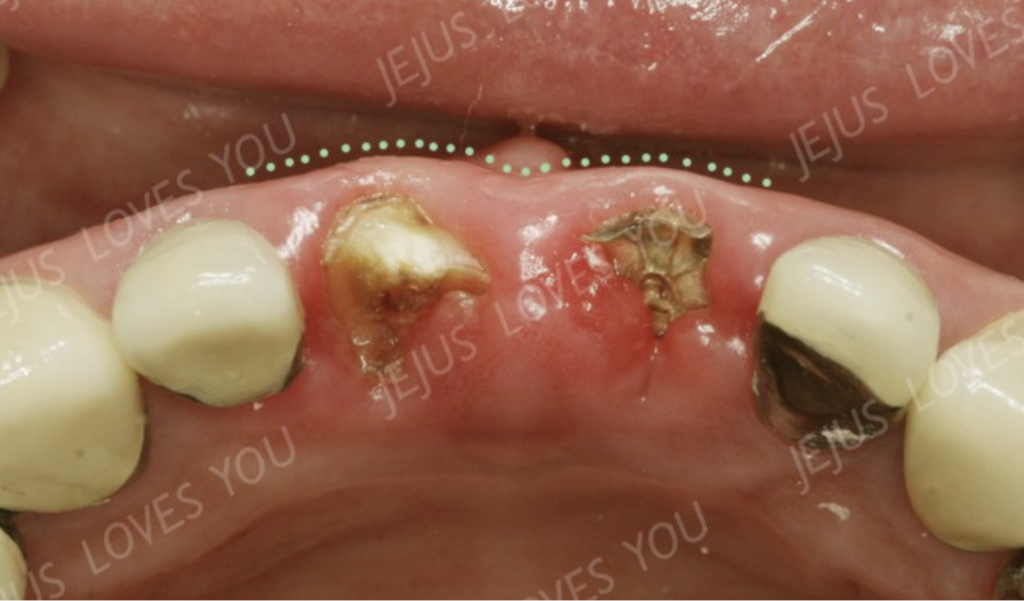

하지만 치아를 뽑고 그냥 방치하게 되면(즉, 브릿지나 메릴랜드, 휴먼브릿지 치료도 동일합니다.) 이렇게 시간이 지나면서 서서히 뼈가 얇아지게 되지요.

사진처럼 치아의 머리가 다 사라진 경우라도 뼈 속에 뿌리만 남아 있다면 뼈의 모양이 유지되고 있을 것을 볼 수 있습니다.